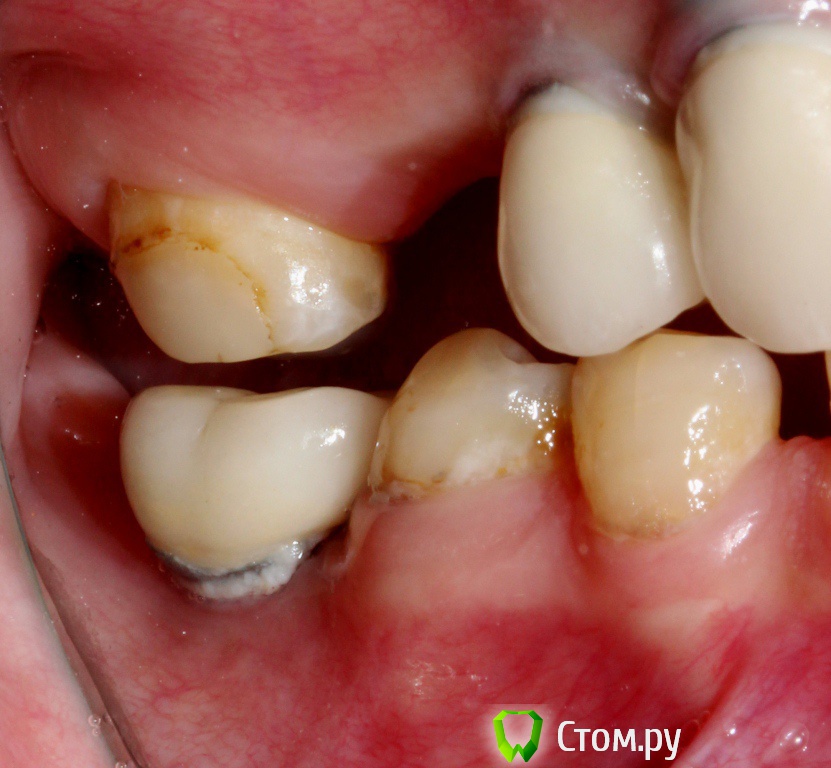

zzkz Опубликовано 27 ноября, 2014 Поделиться Опубликовано 27 ноября, 2014 2 года назад установили имплантаты, ДЦ абатменты и коронки. На сегодня такая ситуация. Имплантаты интегрированы.+ ко всему форма зубов не устраивает(крупные). Налета на фронтальных нет вообще(пользуется ирригатором только во фронте), на нижних дистальных околопришеечный налет и в области них совсем нет ЗКПД. Какая система имплантатов она не знает. Если придется снимать коронки, что посоветуете. Какой набор может универсальный приобрести? Насколько реально закрыть рецессии? В какой последовательности лучше идти? 1 Ссылка на комментарий

ILGAMSA Опубликовано 27 ноября, 2014 Поделиться Опубликовано 27 ноября, 2014 (изменено) это астра13, 11, 21, 23 - широкая платформа 4,512 - узкая платформа 3,0остальные - стандартная платформа 3,5/4,0отвертка обычная от любого израиля подходит.Только торки там другие. Изменено 27 ноября, 2014 пользователем ILGAMSA Ссылка на комментарий

ILGAMSA Опубликовано 27 ноября, 2014 Поделиться Опубликовано 27 ноября, 2014 все можно постараться исправить мягко-тканной аугментацией 1 Ссылка на комментарий